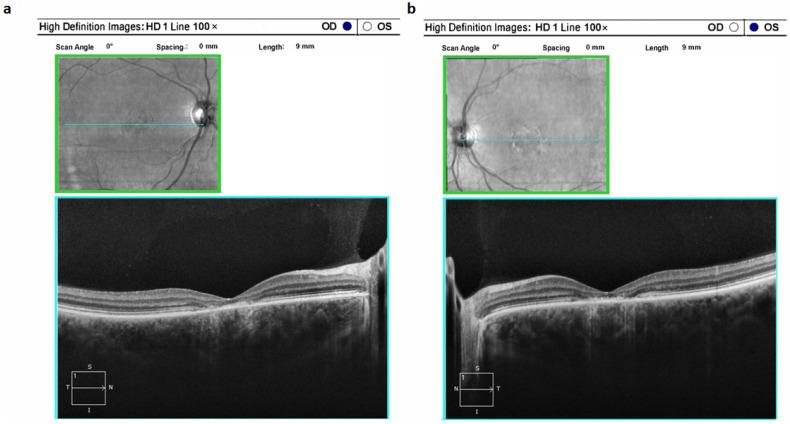

Inherited retinal diseases (IRDs) constitute a prevalent group of inherited ocular disorders characterized by marked genetic diversity alongside moderate clinical variability. Among these, -related eye pathology stands as a prominent form affecting the retina. In this study, we conducted an in-depth analysis of 96 patients harboring variants in the European part of Russia. Notably, the complex allele c.[1622T>C;3113C>T] (p.Leu541Pro;Ala1038Val, or L541P;A1038V) and the variant c.5882G>A (p.Gly1961Glu or G1961E) emerged as primary contributors to this ocular pathology within this population. Additionally, we elucidated distinct disease progression characteristics associated with the G1961E variant. Furthermore, our investigation revealed that patients with loss-of-function variants in were more inclined to develop phenotypes distinct from Stargardt disease. These findings provide crucial insights into the genetic and clinical landscape of -related retinal dystrophies in this specific population.